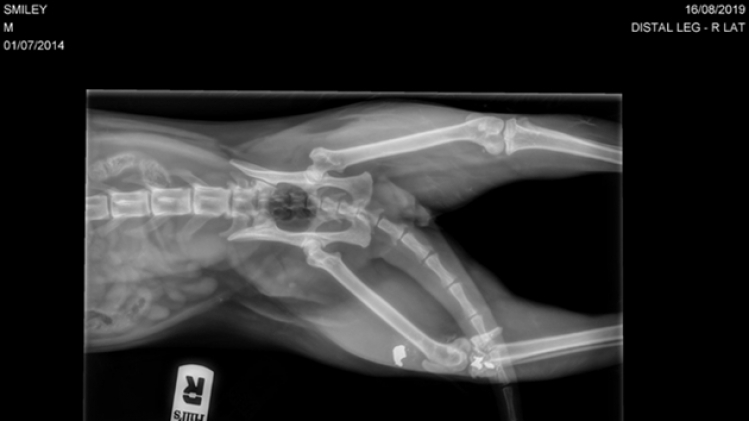

Les clichés issus de la radio passée à la clinique affichent l'impact de la balle. La suite des événements est particulièrement douloureuse pour sa propriétaire.

"Il a été touché au niveau de la cuisse. On ne pouvait pas mettre de visse ou de plaque. L’articulation avait explosé. La balle a été récupérée", précise-t-elle.